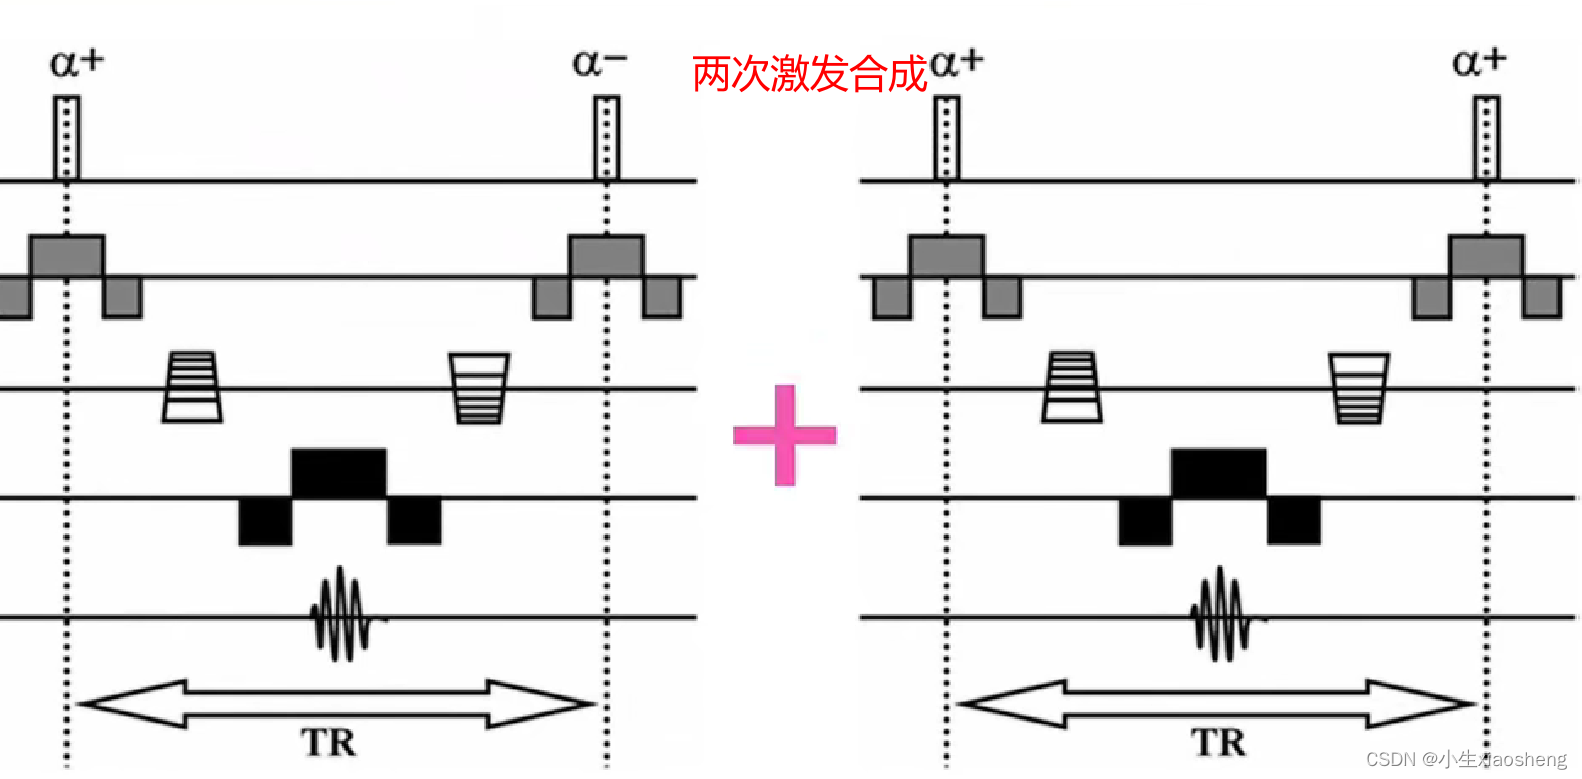

4.双激发平衡SSFP序列

双激发平衡SSFP序列在平衡SSFP的基础上进一步改进,通过两次激发来增强信号并改善图像质量。具体来说,它使用两个连续但相位相反的射频脉冲来激发质子。由于两次激发的相位相反,它们产生的信号在相位上相互抵消,从而减少了由于T1和T2差异导致的信号衰减或增长。这种技术可以提高图像的对比度和信噪比,特别是在需要高信噪比和快速成像的应用中。